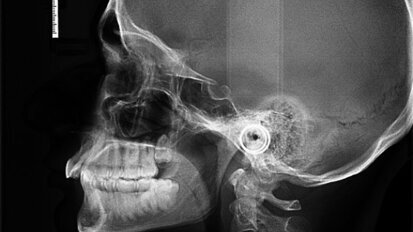

Mastering the implant digital workflow

Whether we like it or not, we are embracing the digital era in our brave new world. Many dental practices are now becoming paper-free—a digital ...